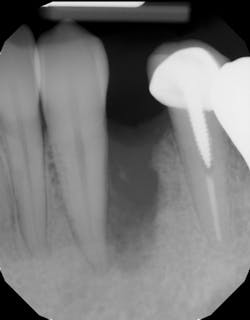

Although unpredictable, a greater amount of alveolar ridge loss following extraction usually occurs in the horizontal dimension and affects the buccal bone of the ridge.3 In fact, 50% of alveolar bone dimension can be lost after tooth extraction, with losses reported of up to 6–7 mm (figure 1). Two-thirds of this loss of bone volume can occur within the first three months of tooth extraction.4

Because of this alveolar resorptive pattern after tooth extraction, bone grafting the extraction socket after tooth extraction procedures has become a solution that attempts to limit the amount of hard- and soft-tissue loss. There are many systematic reviews in the literature that compare the results of residual ridge dimension following tooth extraction after the use of a bone graft (with or without a membrane) versus extraction alone without grafting.7

• preserving tissue structure for subsequent dental implant therapy.Decision matrix